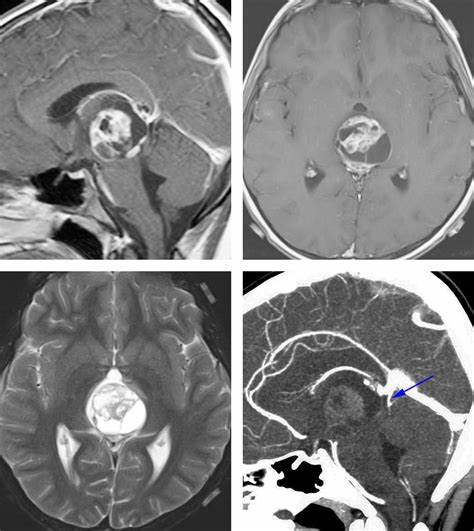

11.三侧性视网膜母细胞瘤:视网膜母细胞瘤是儿童眼内常见的恶性肿瘤。该肿瘤通常在幼年期被诊断,通常在2岁以前。CT扫描可观察到钙化,组织学检查中,钙化见于95%的视网膜母细胞瘤。三侧性视网膜母细胞瘤一词是指存在双侧视网膜母细胞瘤,伴有相关的中线原发性颅内肿瘤(通常在松果体区域,偶尔在鞍上或鞍旁区域)。约2-11%的双侧视网膜母细胞瘤患者存在这种共存的颅内肿瘤。

12.Galen静脉血管瘤:脉络膜型动静脉畸形,累及Galen静脉。它是动脉瘤引起动静脉血液分流的结果。其发生于胎龄6-11周,表现为持续性胚胎前脑Markowski静脉。Markowski静脉实际上注入Galen静脉